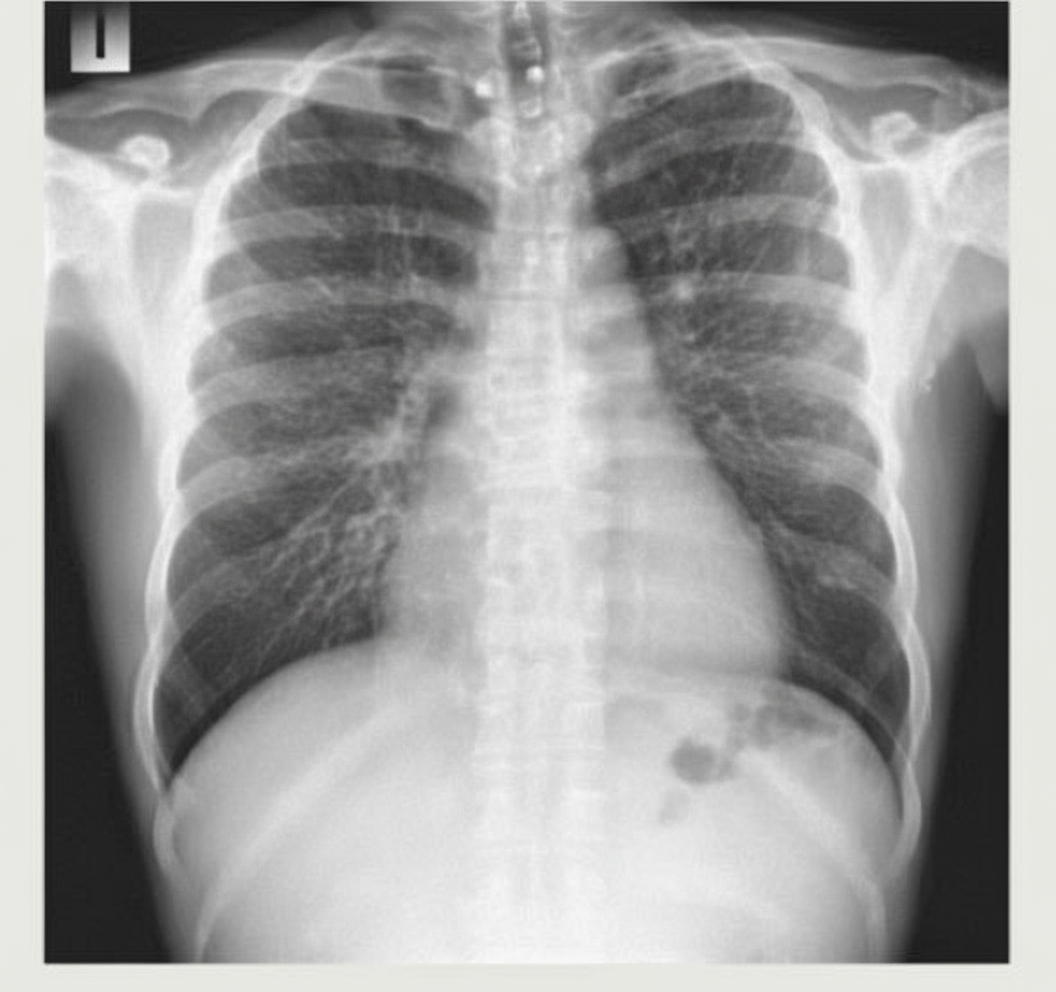

A chest X-ray shows bilateral reticular nodular shadows in both lung fields. The diaphragm is not flattened and the cardiothoracic ratio appears normal. What is the most likely pattern seen?

Explanation: ***Reticular shadows*** - The CXR shows **bilateral reticular nodular shadows** without hyperinflation or cardiac enlargement - This pattern represents **thickened interstitial structures** forming a net-like (reticular) appearance - Characteristic of **interstitial lung diseases** such as idiopathic pulmonary fibrosis, interstitial pneumonitis, or collagen vascular disease - Normal cardiothoracic ratio and diaphragm position confirm this is an **interstitial pattern** *Incorrect: Emphysema* - Emphysema presents with **hyperinflation** and **flattening of the diaphragm** - Would show increased lucency, not reticular shadows - The normal diaphragm position rules out significant emphysema *Incorrect: Pulmonary edema* - Pulmonary edema typically shows **bat wing or perihilar distribution** - Associated with **increased cardiothoracic ratio** and **Kerley B lines** - The normal cardiac borders argue against cardiogenic pulmonary edema *Incorrect: Pericardial effusion* - Pericardial effusion presents with **enlarged cardiac silhouette** (water bottle heart) - **Increased cardiothoracic ratio** would be prominent - Does not produce reticular nodular lung field shadows - Normal cardiac borders on this CXR exclude significant pericardial effusion